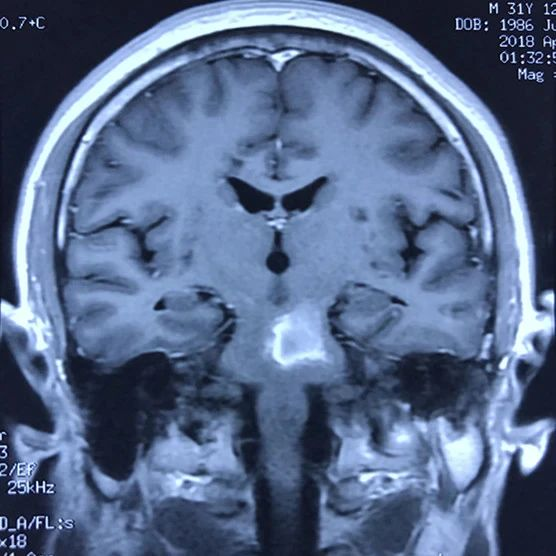

病人多发脑海绵状血管畸形,本次出血部位位于桥脑。第一次出血,术前偏瘫,转入我病房时为出血一月左右,采取颞下岩前入路切除脑干病变,术后病人肢体肌力较术前有提高,目前尚未出院。

本次手术资料: